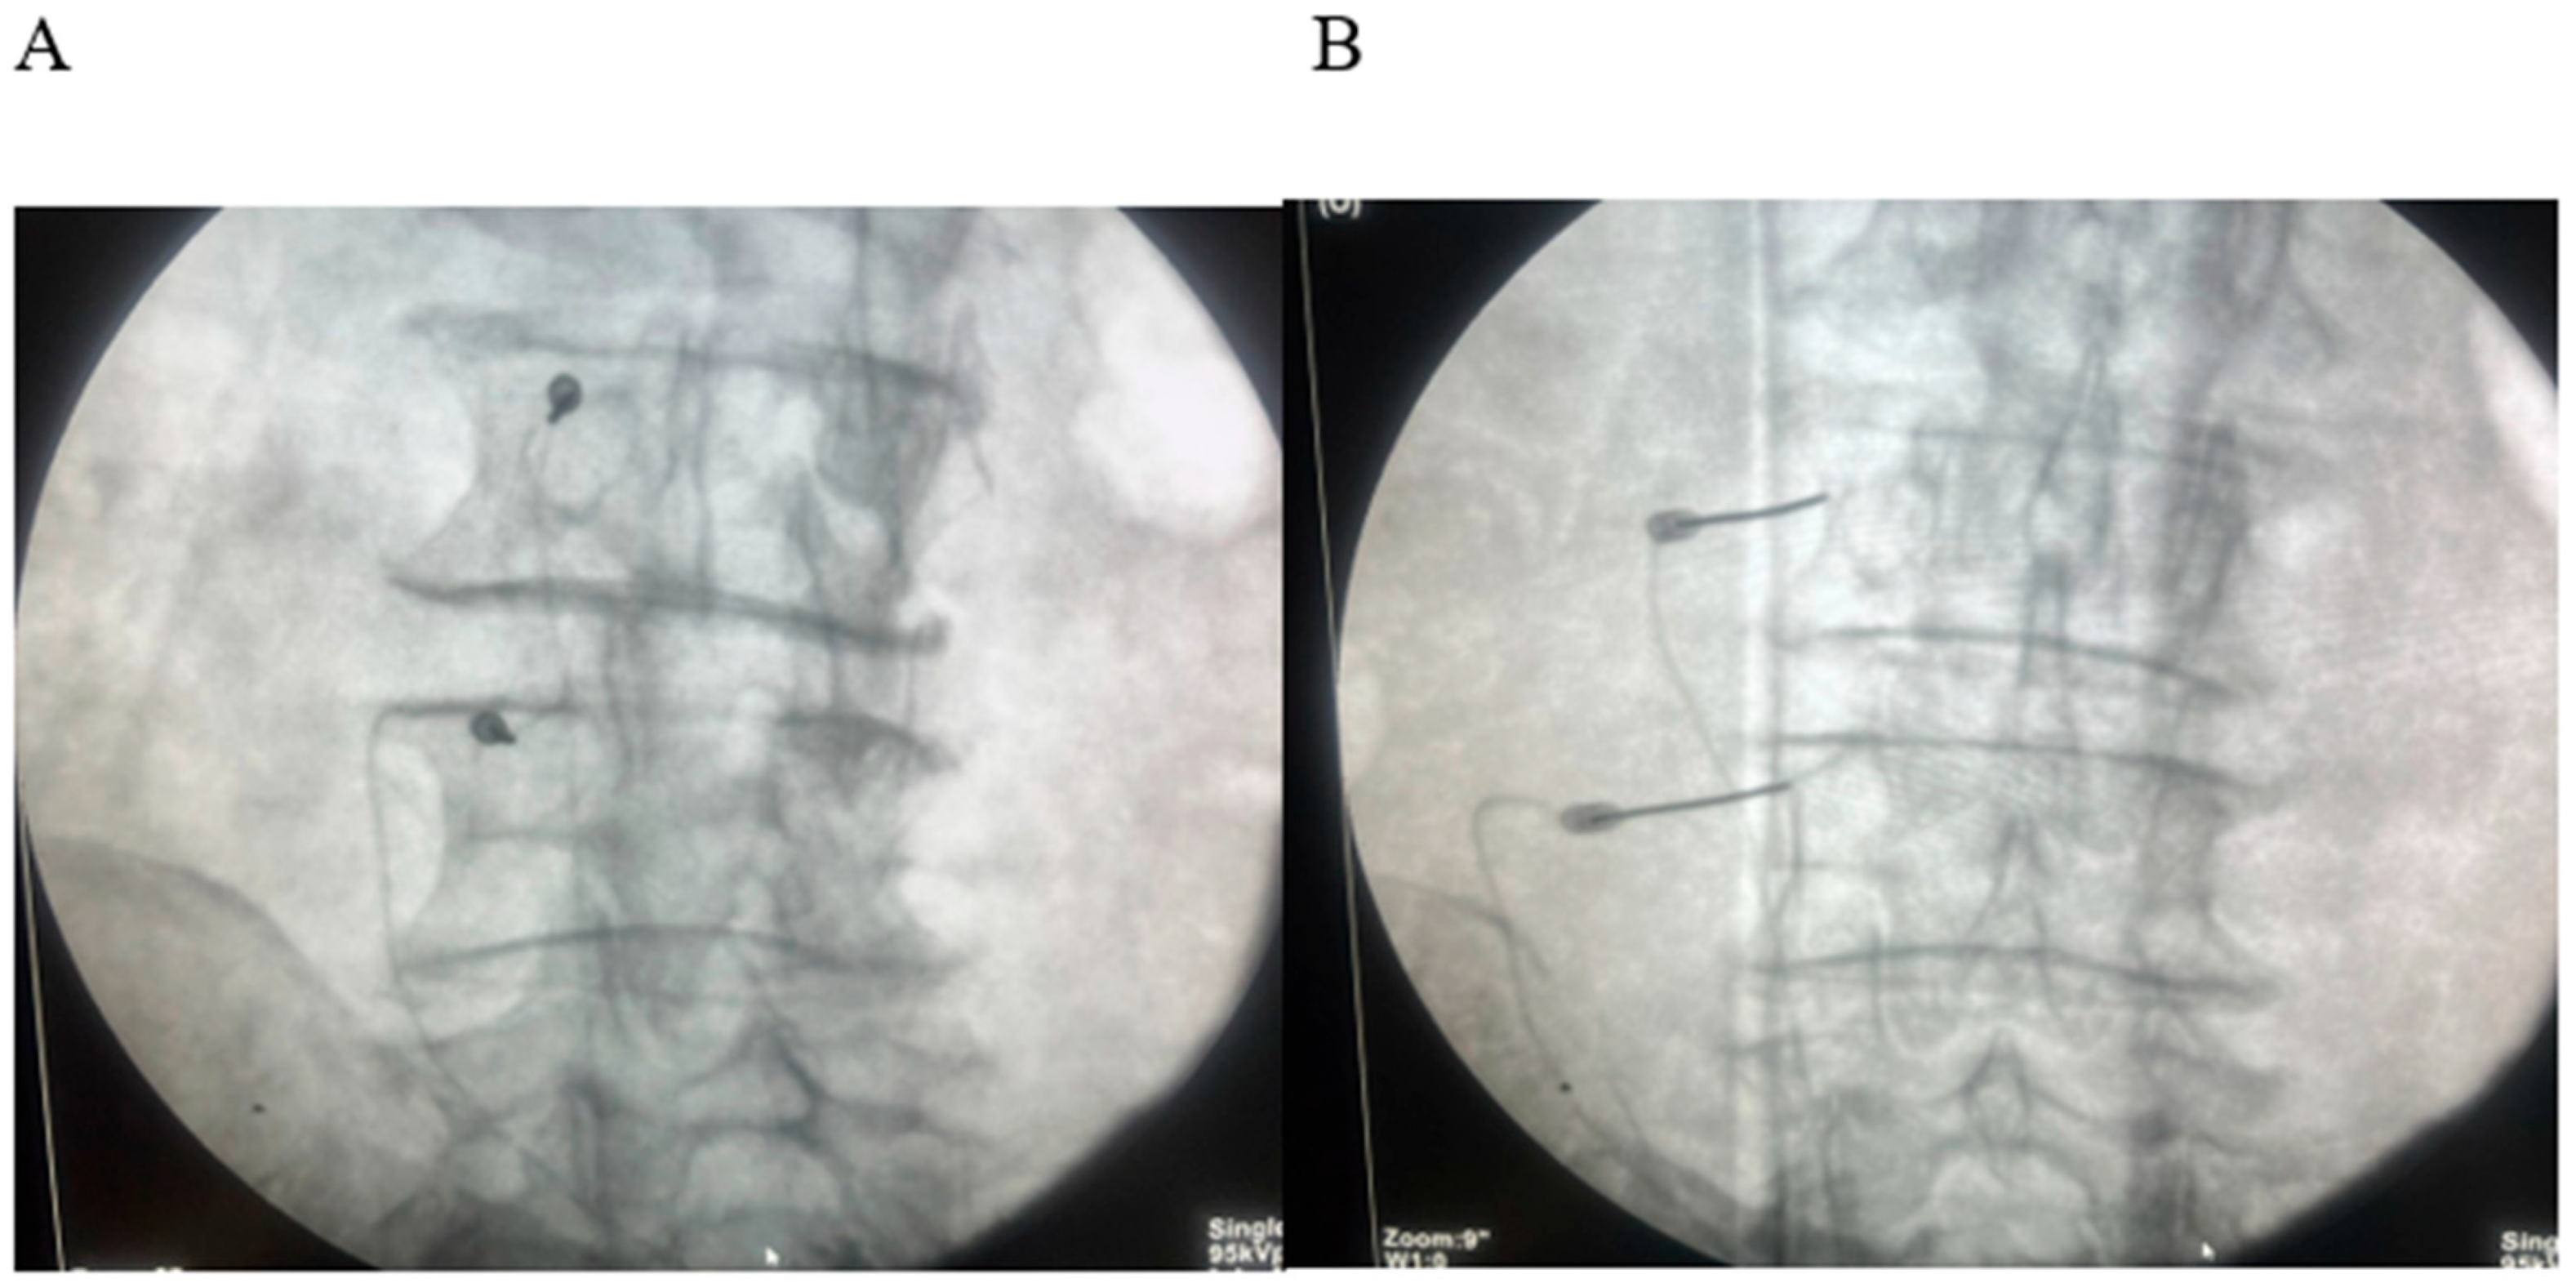

2.3. Procedures